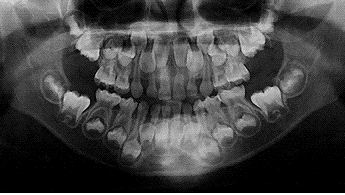

レントゲンは見えている歯だけでなく、歯茎に埋まった歯や歯茎の状態、骨格部分の骨の状態など、歯を支える土台の部分の状況を確認できます。噛み合わせや見た目のバランスを考えた歯列矯正が叶うのです。

例えば、歯列矯正で改善が期待できる出っ歯は、歯だけでなく顎の骨が影響していることもあるため、目視だけでは正しく治療方針を決めることができません。